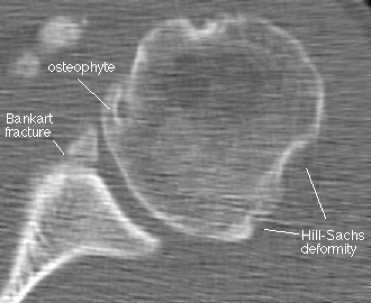

Наиболее типичным (около 85% передних смещений травматической этиологии) является повреждение Банкарта – отрыв фиброзного или фибрознохрящевого фрагмента от края суставной впадины в месте прикрепления связки к суставной впадине с повреждением суставной губы. Кроме того, травма может приводить и к костным повреждениям – перелому гленоидного кольца спереди, костному повреждению Банкарта (то есть повреждению Банкарта в сочетании с переломом) и перелому большой бугристости.

МРТ плечевого сустава. Корональные Т1-взвешенные МРТ. Переломы Хилла-Сакса и Банкарта.

КТ плечевого сустава, Переломы Банкарта и Хилла-Сакса.